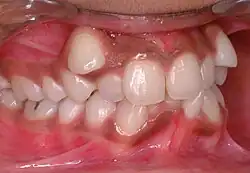

| Malocclusion in 10-year-old girl | |

In orthodontics, a malocclusion is a misalignment or incorrect relation between the teeth of the upper and lower dental arches when they approach each other as the jaws close. The English-language term dates from 1864;[1] Edward Angle (1855–1930), the "father of modern orthodontics",[2][3] popularised it. The word derives from mal- 'incorrect' and occlusion 'the manner in which opposing teeth meet'.